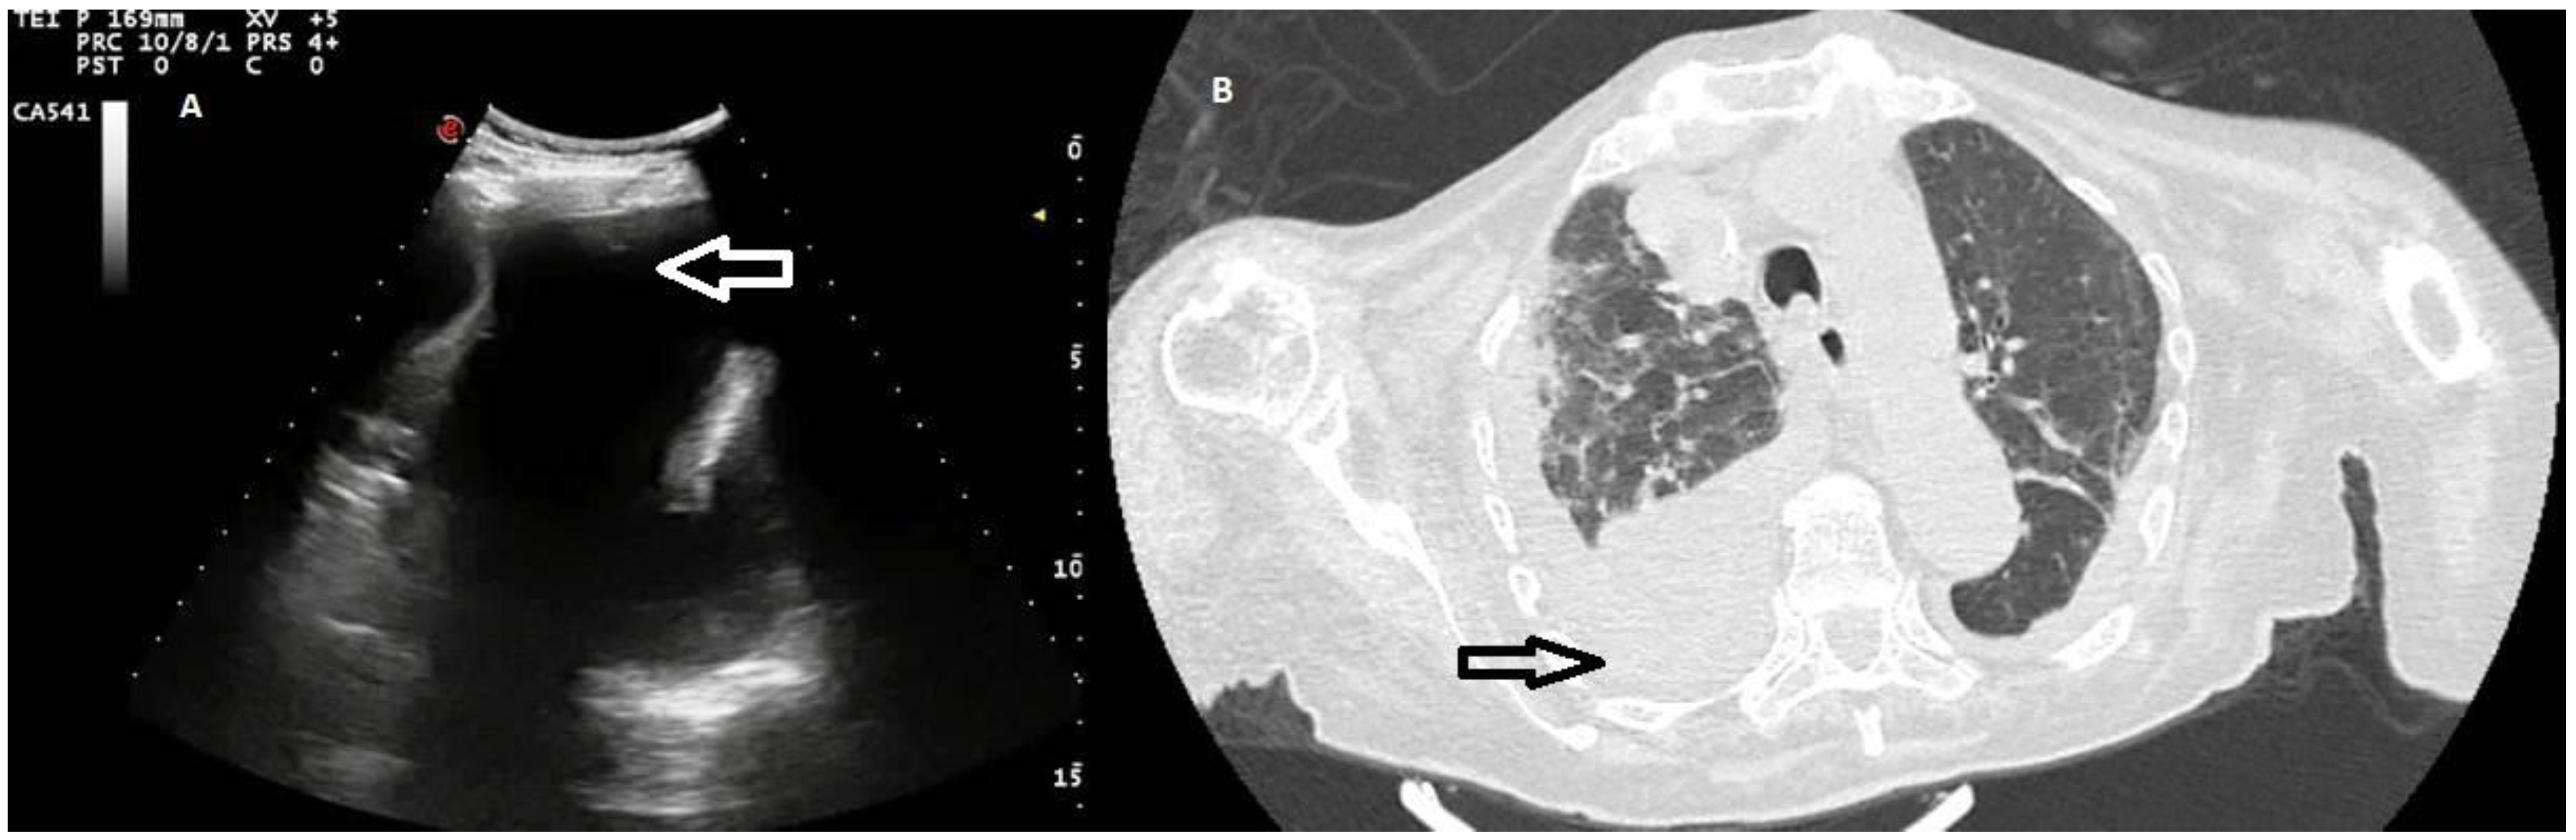

Six of the 33 effusions (18.18%) presented by patients diagnosed with heart failure were classified as exudates. Such effusions presented a complex nonseptated appearance on TUS examination (Figure 5).

Figure 5. (A) TUS scan showing a complex nonseptated effusion with consensual parenchymal atelectasis. The tip of the needle during TUS-guided thoracentesis with a multifrequency convex probe (3.5 MHz) is highlighted by a white arrow. (B) The corresponding CT scan shows an extensive apico-parieto-basal pleural effusion of greater right expression (black arrow) with consensual lower lobe atelectasis. A bilateral thickening of interlobular septa and some right ground-glass opacities with partial sparing of the lung periphery are also present (congestive heart failure).